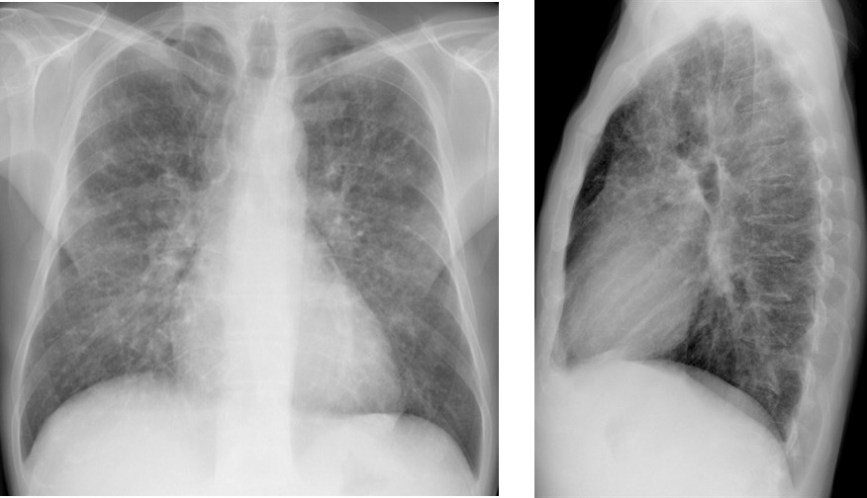

CASO: Febrícula y tos de 4 días de evolución.

Hallazgos:

- En la placa PA se observa una asimetría en los hilios pulmonares, el hilio izquierdo tiene una densidad aumentada.

- Tras examinar la placa lateral se observa un aumento de densidad en la columna que puede ser compatible con una condensación, es el signo de la desnificación vertebral.

SIGNO DE LA DENSIFICACIÓN VERTEBRAL: En la radiografía lateral normal, la densidad de la columna torácica tiende a disminuir desde la parte superior hasta el diafragma; la alteración de ese patrón por la presencia de una densidad superpuesta a la columna, indica la existencia de una consolidación pulmonar. Este signo adquiere especial valor cuando en la proyección posteroanterior la consolidación está oculta en el espacio retrocardíaco o en la base pulmonar.